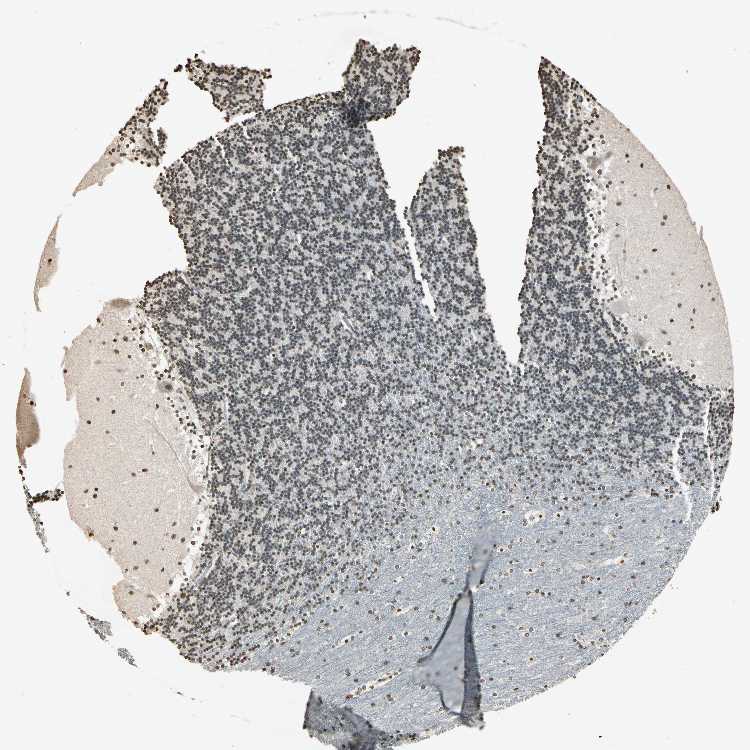

CEREBELLUM - Antibody stainingi

Antibody staining in the annotated cell types in the current human tissue is reported as not detected, low, medium, or high, based on conventional immunohistochemistry profiling in selected tissues. This score is based on the combination of the staining intensity and fraction of stained cells.

Each image is clickable and will lead to virtual microscopy that enables deeper exploration of all samples and also displays staining intensity scores, fraction scores and subcellular localization as well as patient and tissue information for each sample.

Antibody HPA019039Antibody CAB009058

Purkinje cells MediumLow

Cells in granular layer HighMedium

Cells in molecular layer HighHigh